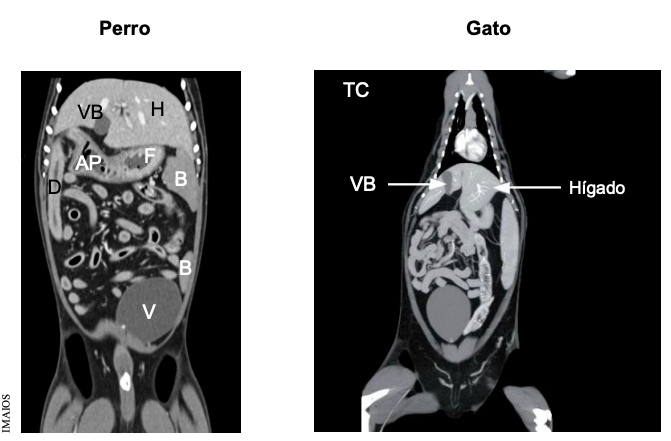

Topogradía abdominal del perro: Tac o TC del tejid blando, vista dorsal

Generalmente las imagenes de tac están espejadas

En gato el bazo siempre esta en la izquierda, el perros la cola puede estar a la derecha

IMAIOS para repasar imagenes de tac